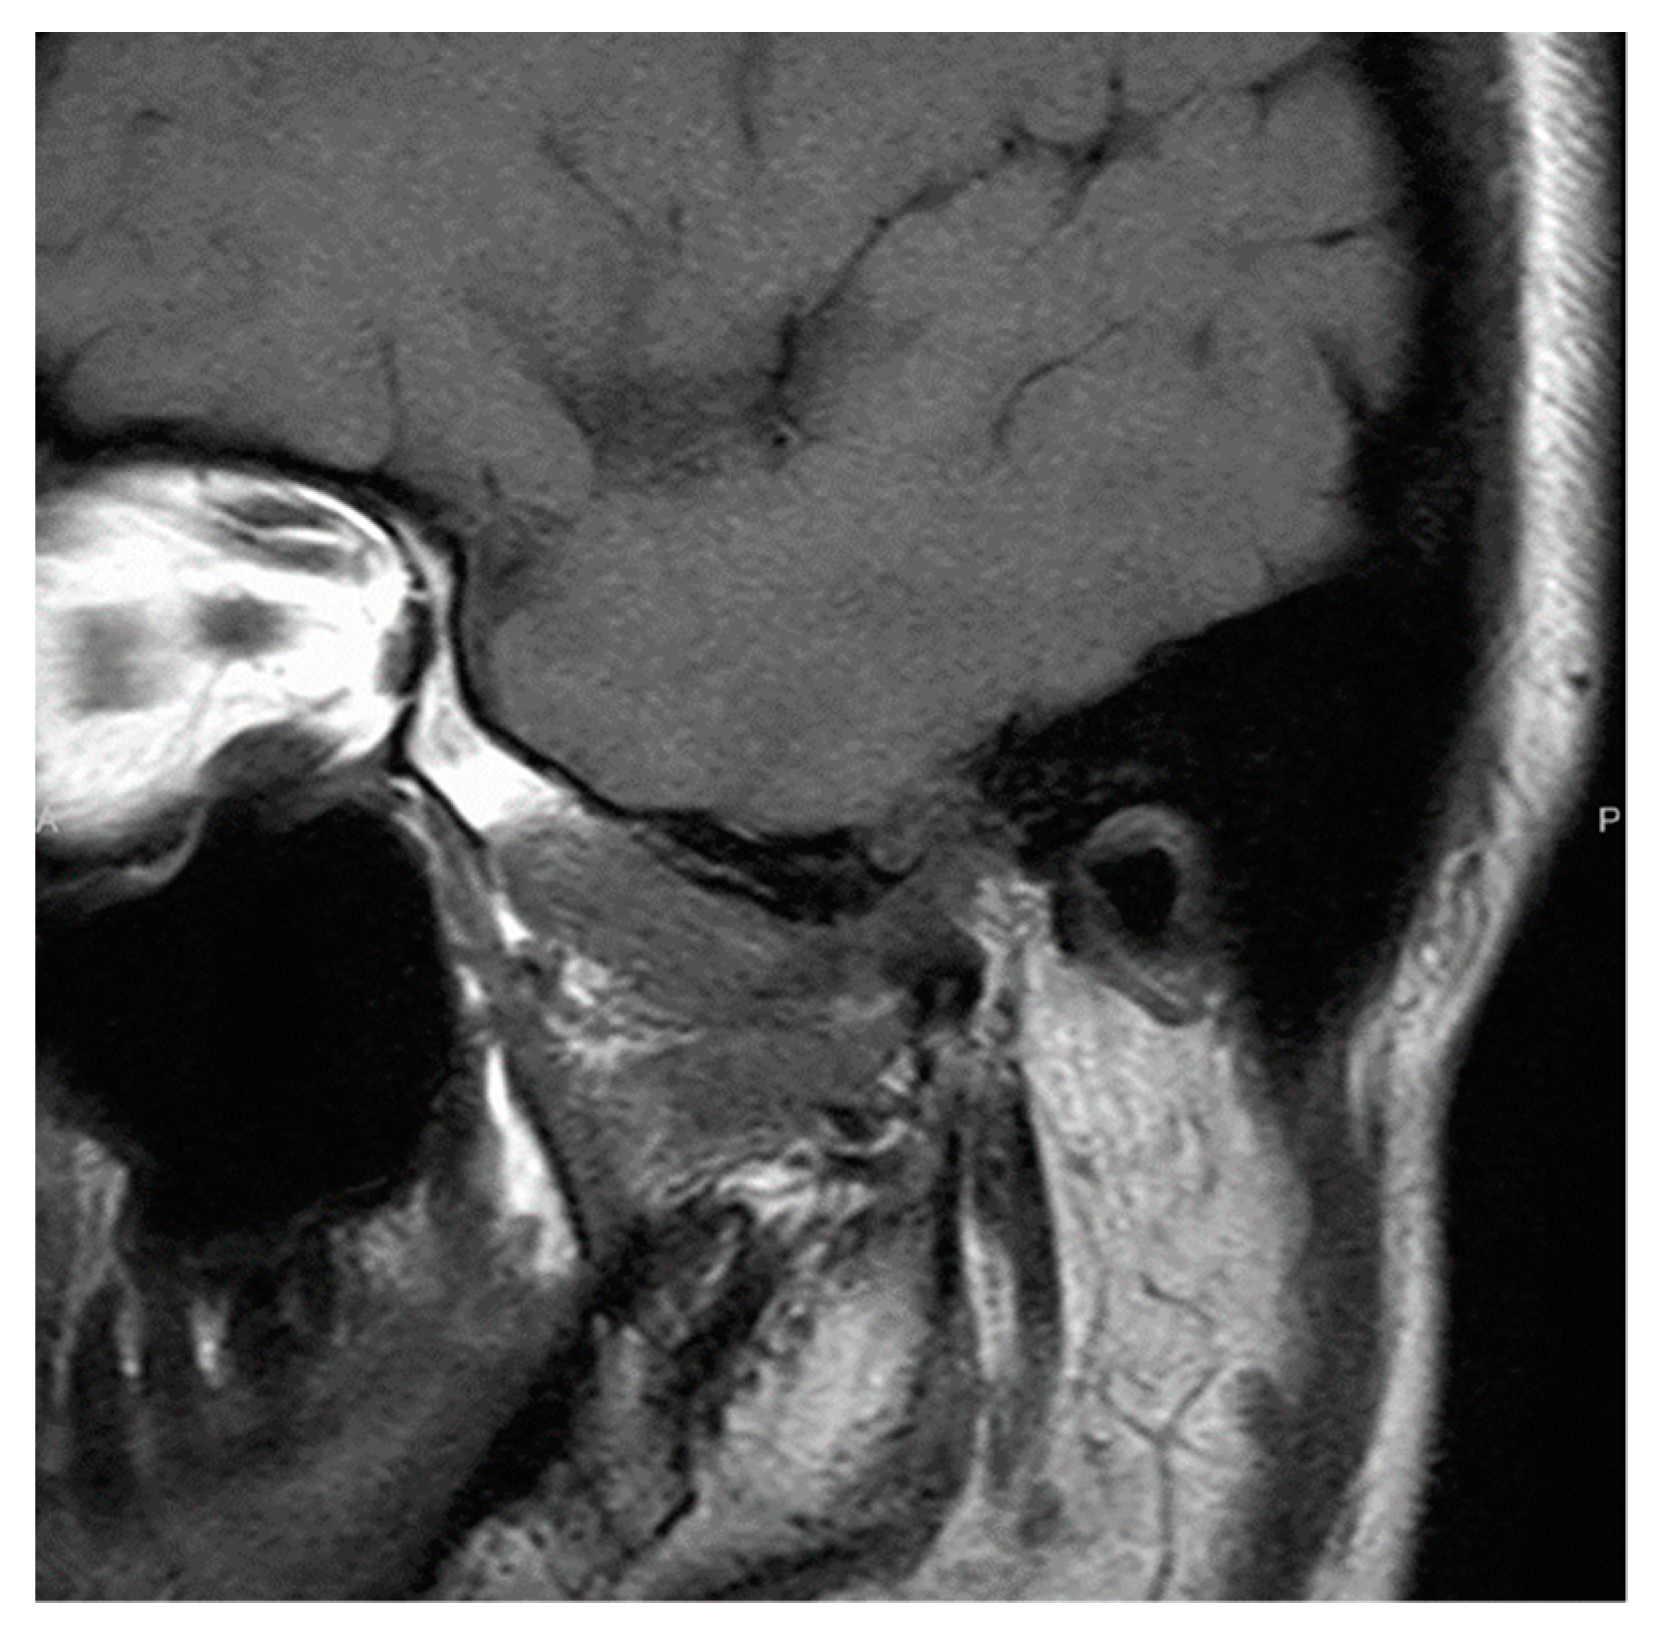

2.2. Patient 2